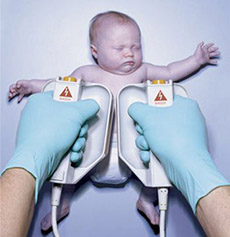

先天性甲状腺功能减低症

疾病介绍:先天性甲状腺功能减低症(简称甲低)又称克汀病或呆小病,多见于先天甲状腺缺陷,主要表现为体格和精神发育障碍,早期诊断和治疗可防止症状的发生或发展…【详细】